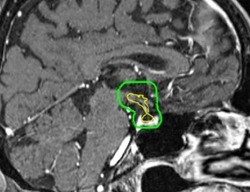

Cognitive impairment and fatigue are common side effects of whole brain irradiation (WBI) comprising the quality of life (QoL) for survivors. While the former is related to radiation-induced hippocampal injury, the latter could be secondary to hormonal disbalance as a consequence of radiation of the HT-P area. Thus, sparing both regions from higher irradiation doses could reduce these sequelae. In this article, Stefan Janssen et al. work to quantify the prevalence of brain metastases involving the hypothalamic-pituitary (HT-P) area.